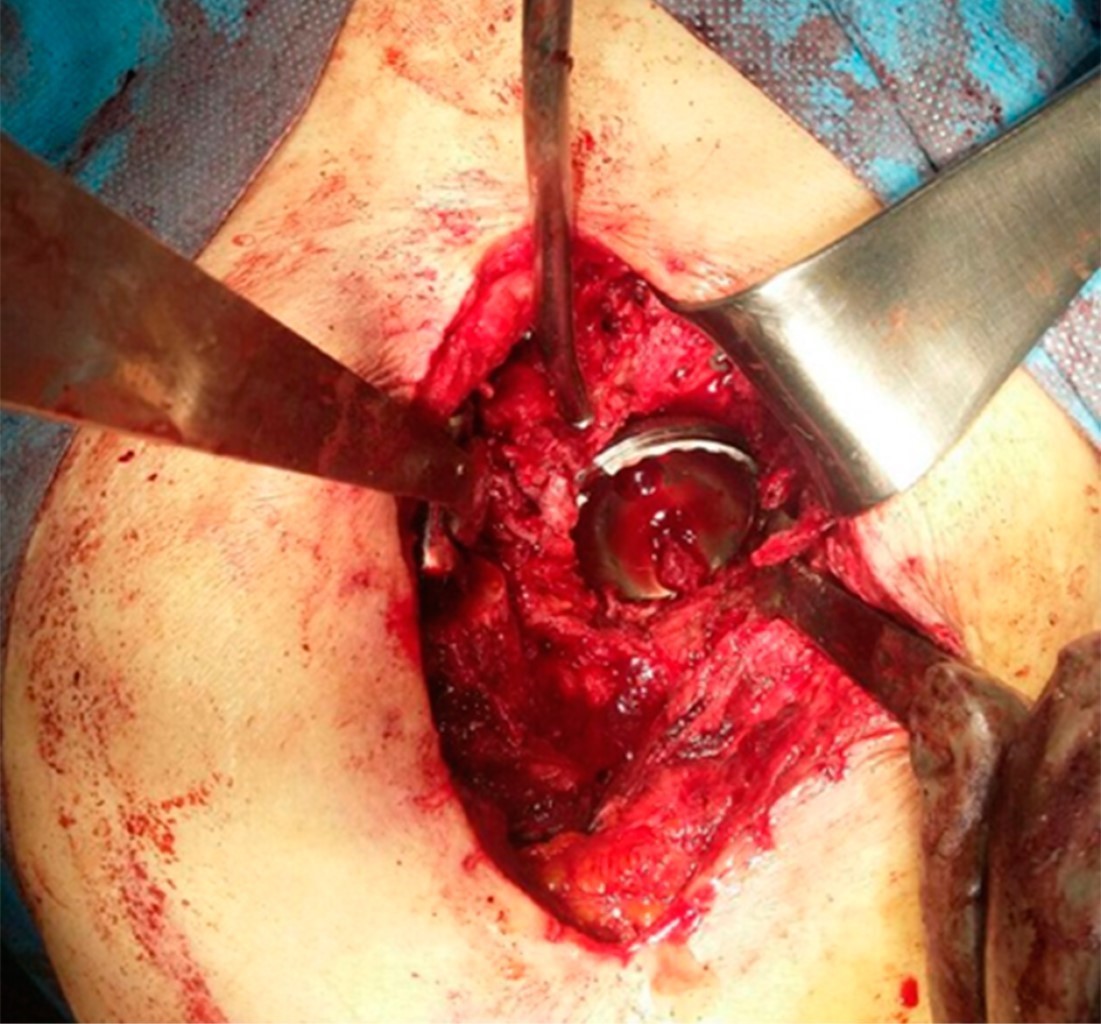

Paciente femenino de 71 años que se somete a artroplastía primaria total de cadera derecha secundaria a coxartrosis, con un resultado quirúrgico no satisfactorio en radiografía de control al finalizar la colocación de los componentes debido a una mala orientación del componente acetabular (Figuras 1 y 2), dejando una zona de pérdida en el techo acetabular original. Se decide en ese momento la conservación de la cabeza femoral en tejidos blandos para colocar como injerto en segundo tiempo quirúrgico (Figura 3), el cual se realizó dos semanas posteriores al primer procedimiento, reconstruyendo defecto con injerto de cabeza y fijándolo con tornillos acetabulares 6.5 mm. El componente acetabular constó de una copa Refletion (Smith & Nephew, Memphis, TN, USA) de recubrimiento poroso fijada con tres tornillos acetabulares 6.5 mm y vástago no cementado Synergy (Smith & Nephew, Memphis, TN, USA).

Figura 3